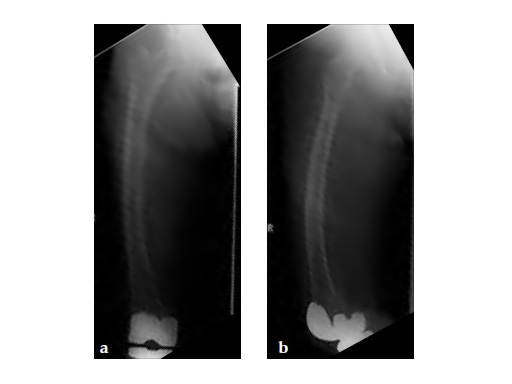

Notice the fracture decrease the emphasis on the anterolateral bow of the femur (See Fig 5a-b).

Insertion of A2FN as patient may be suffering from a stress fracture related to long term (2.5 years) bisphosphonate use. My rationale against a plate is because bisphosphonate related fractures will heal extremely slowly. In our experience even despite bone grafting union may need up to 2 years. In that time, a plate will fail in less than a year even if the patient is only allowed very minimal weight bearing.

Note despite the increased in curvature compared to other nails in the market, there is still noticeable malreduction at the fracture site (see Fig 6a-b).

Patient was allowed and achieved immediate weight bearing and in 6 weeks callus is seen at the fracture site (see Fig 7a-b).